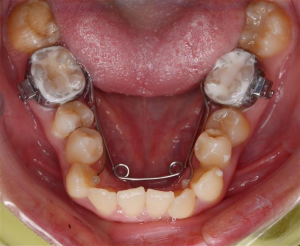

3. Có thể nong hàm dưới hay không?

Đối với chỉnh nha, nong hàm chủ yếu sử dụng cho hàm trên nhưng vẫn có trường hợp dùng được cho hàm dưới gọi là bihelix. Tuy nhiên hiệu quả mang lại không cao như khi nong hàm trên. Bên cạnh đó, bệnh nhân cần được đánh giá chi tiết chất lượng xương, khoảng thiếu răng trên cung hàm cũng như sức khỏe của răng và lợi trước khi thực hiện thủ thuật nong hàm dưới.

Bihelix: Khí cụ nong hàm dưới thường dùng